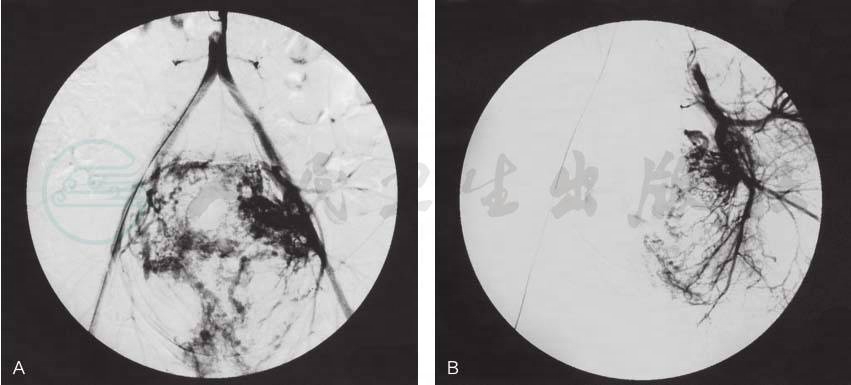

外阴阴道转移瘤经上述方法治疗后,一般均能完全消失,很少复发。转移瘤消失后,局部很少遗留瘢痕(图1)。

图1外阴阴道转移瘤

引自:宋鸿钊滋养细胞肿瘤学(第4版).第4版.ISBN:978-7-117-30225-8.主编: